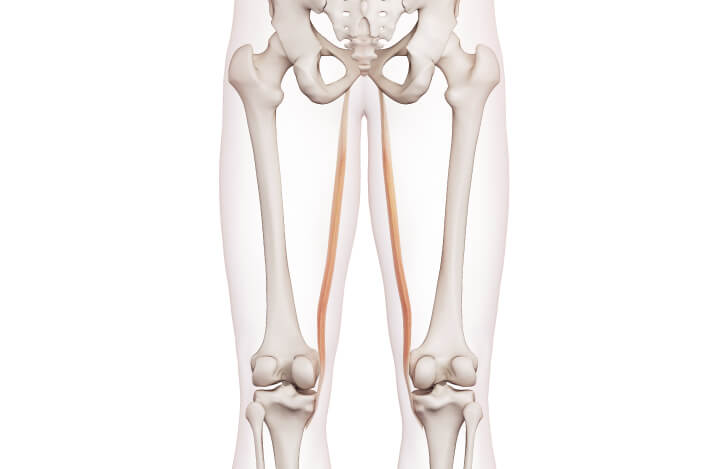

薄筋

大内転筋、長内転筋とは違い、膝関節屈曲の作用もある二関節筋です。薄筋の停止部位は脛骨にあります。

薄筋のオーバーユースにより、付着部の脛骨内側(膝関節の内側)に痛みが出現する疾患を、鵞足炎(がそくえん)といいます。補足情報として、この筋肉は前十字靭帯再建術後の再建靭帯として活用されるケースが多ことも覚えておきましょう。